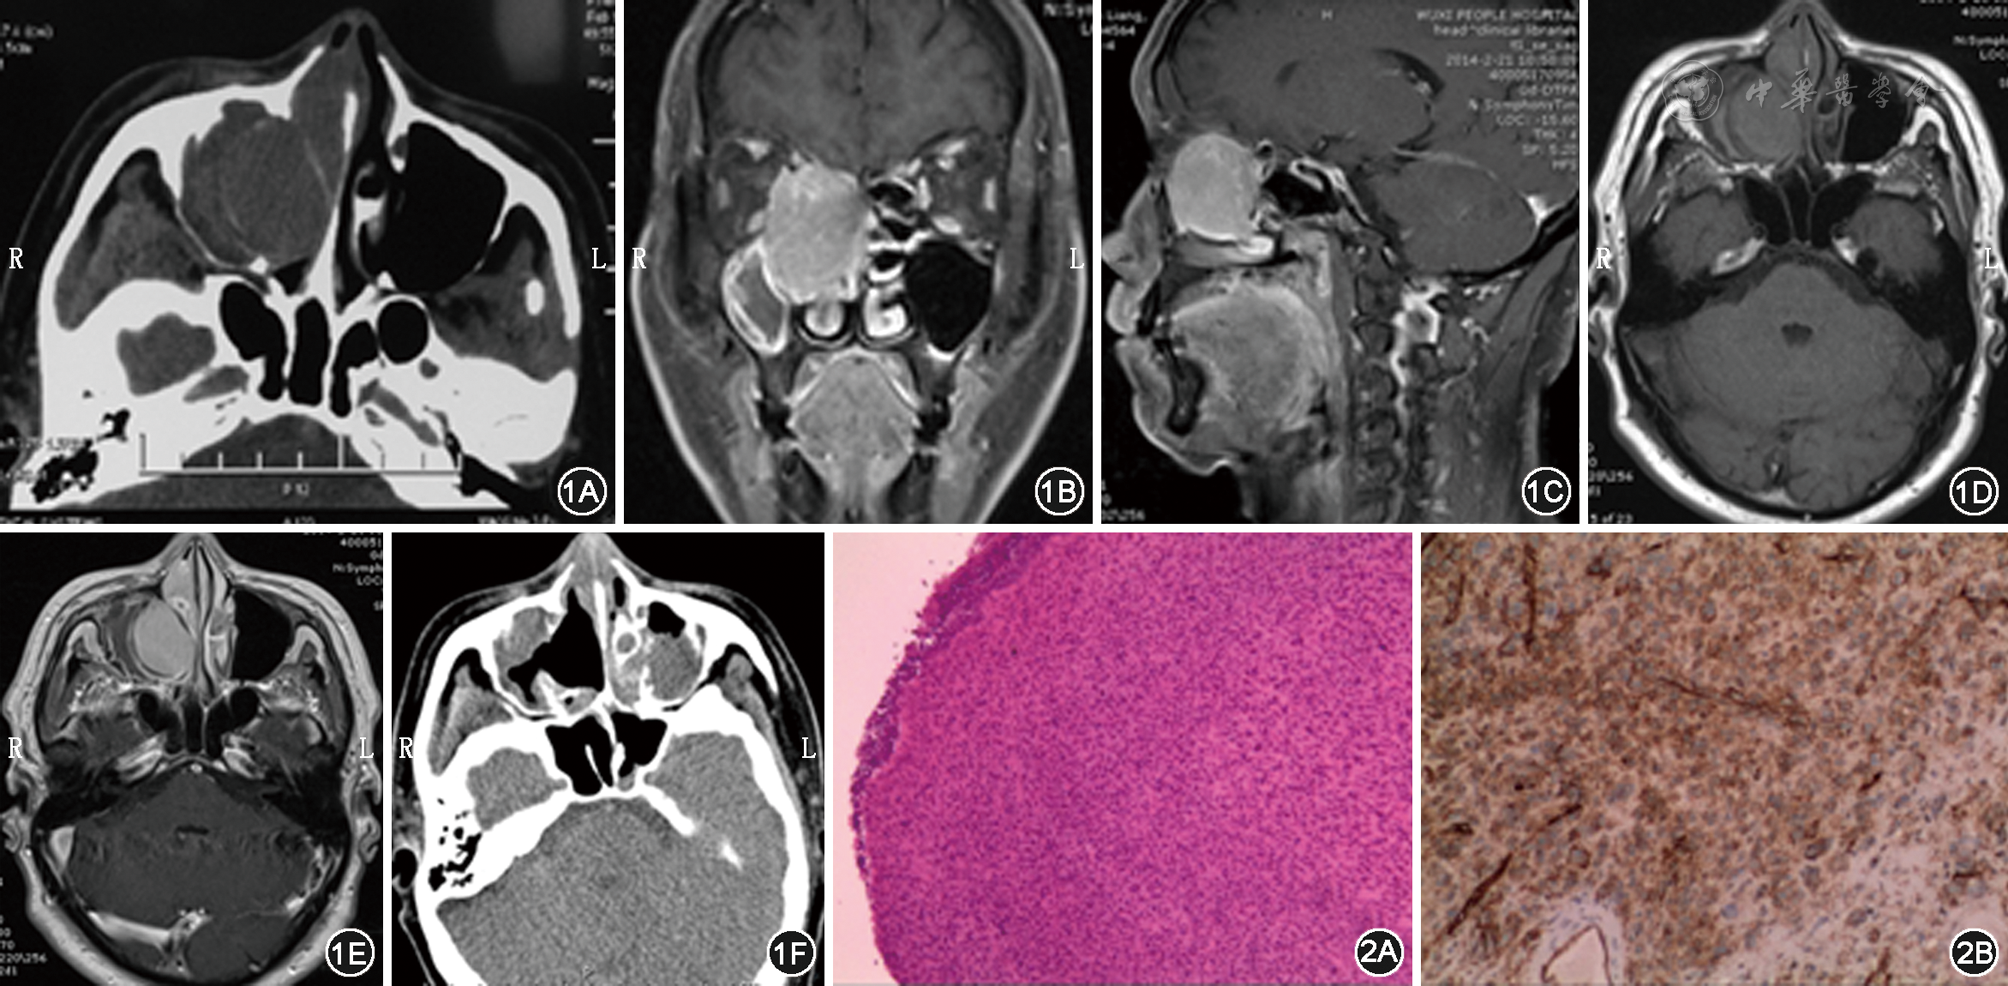

鼻腔恶性孤立性纤维性肿瘤一例 - 中华耳鼻咽喉头颈